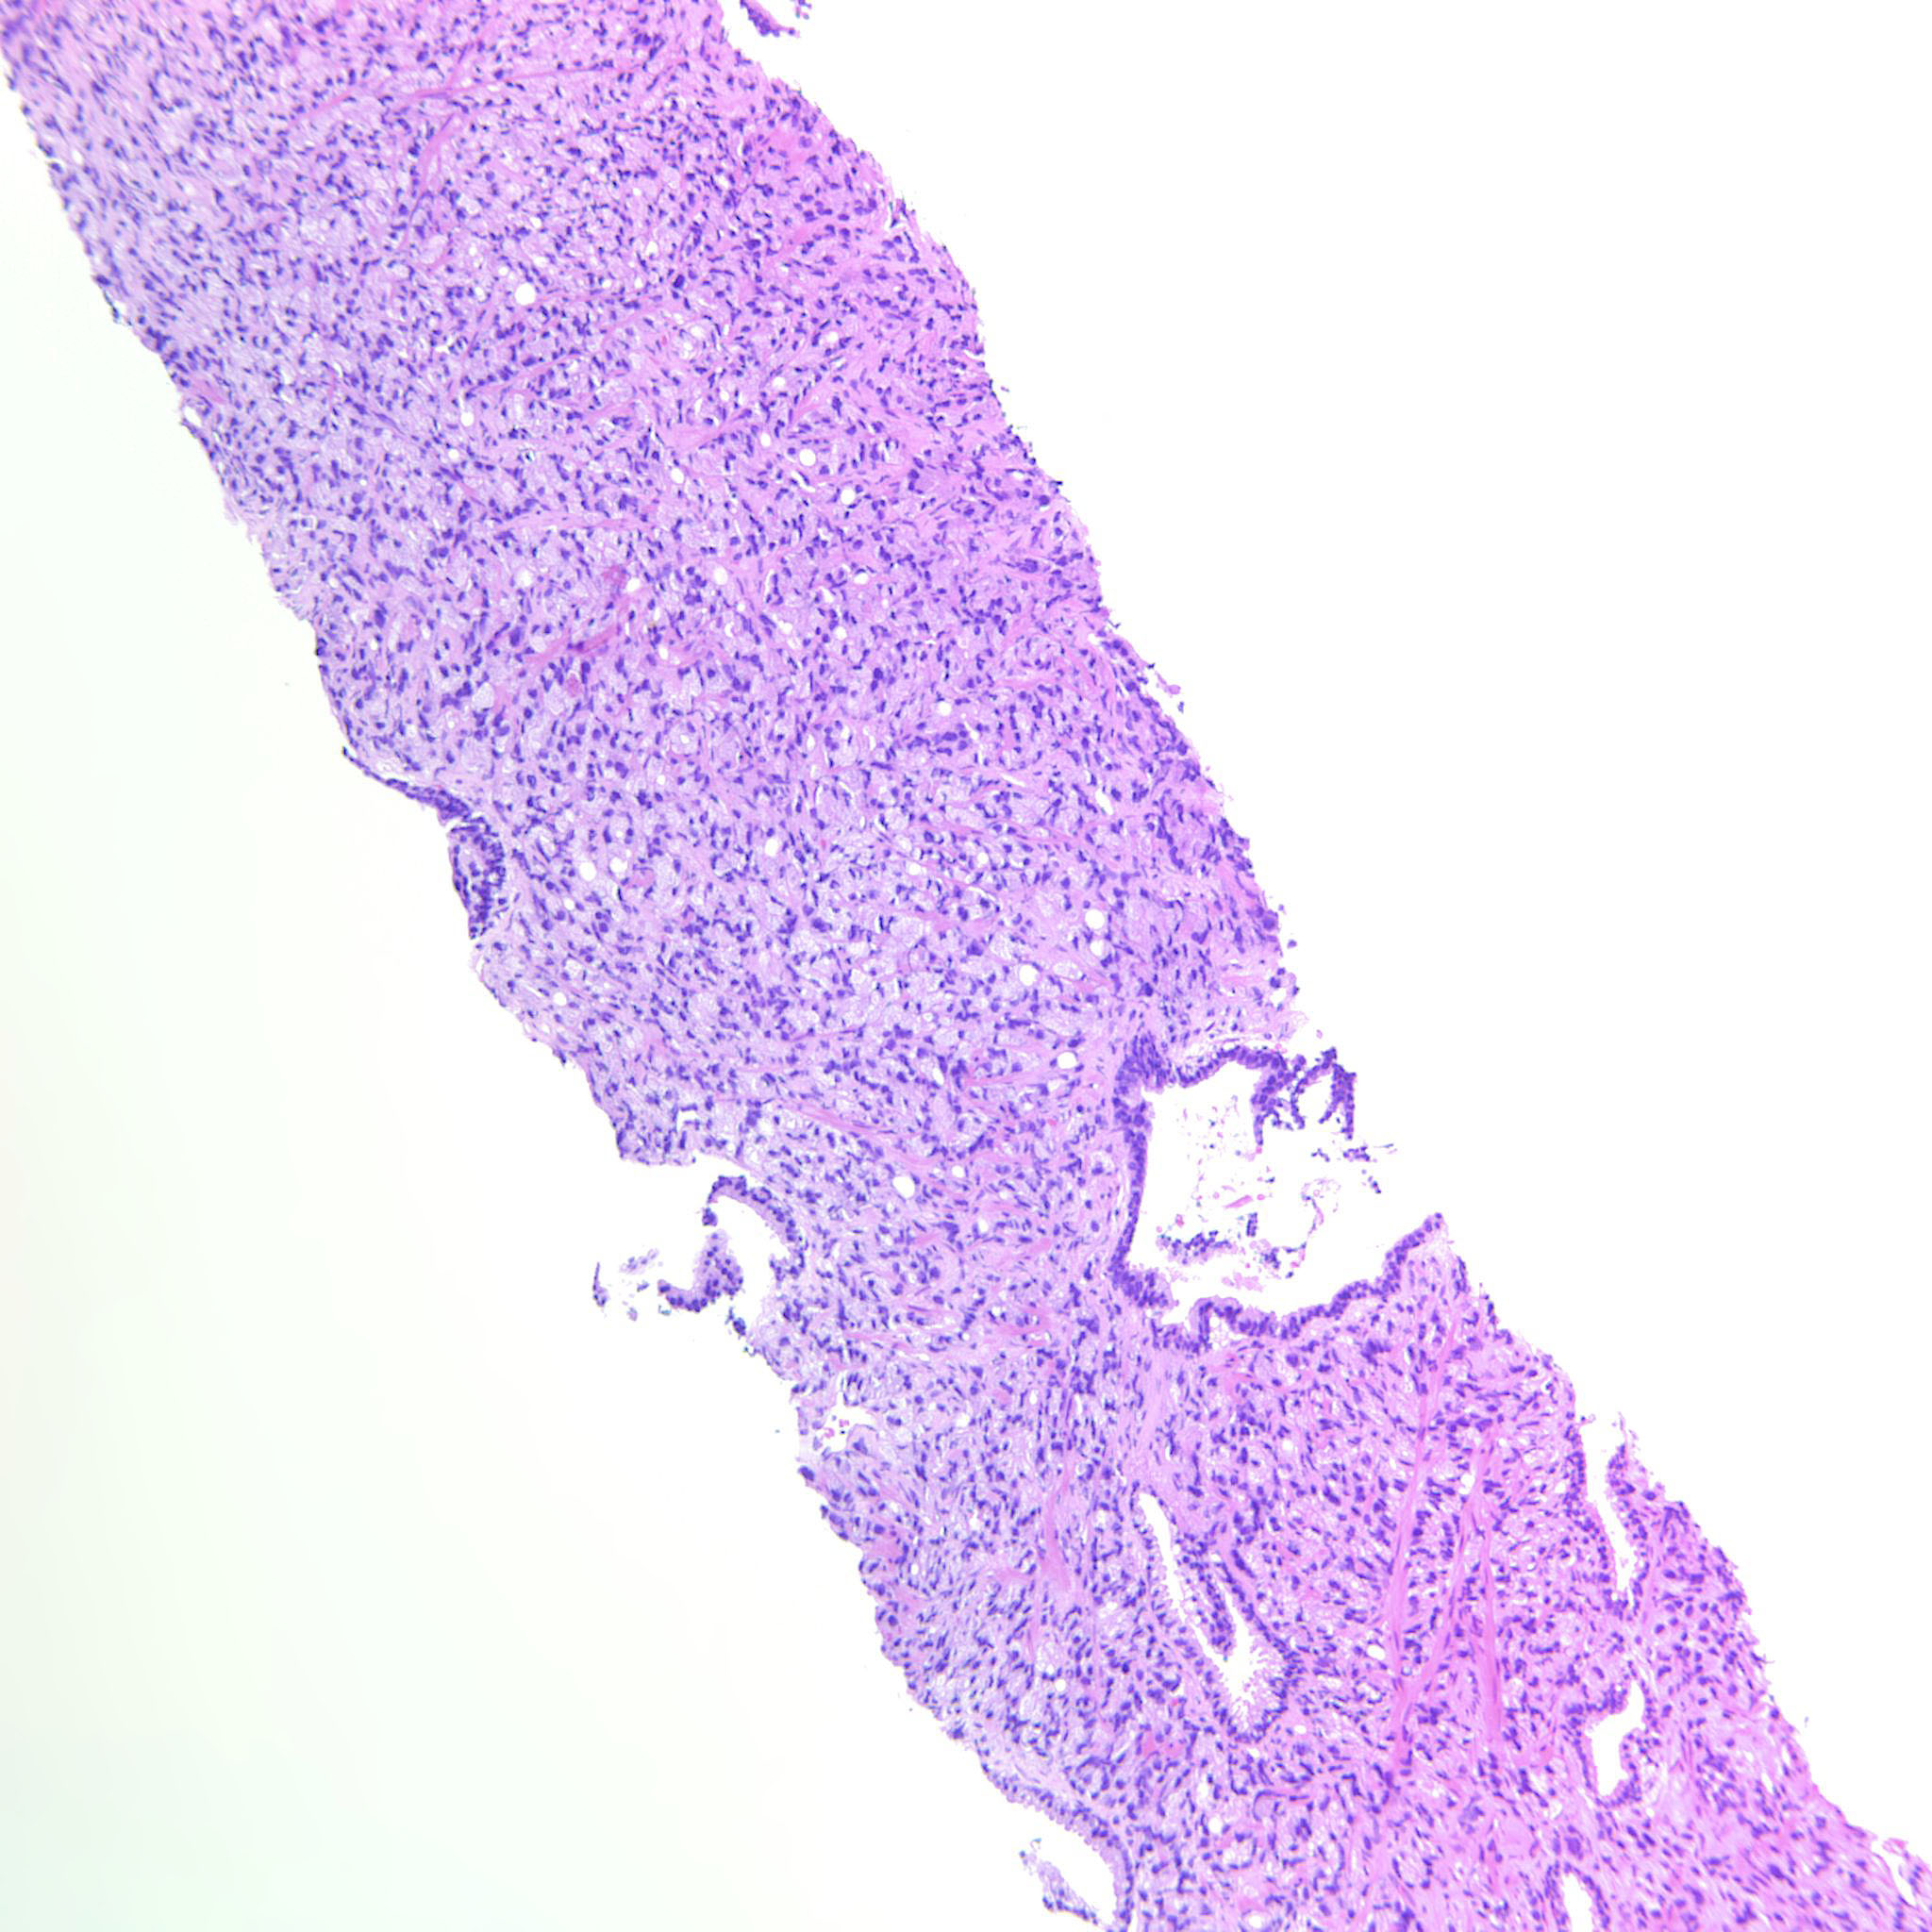

Consensus grade: GS 9-10 (ISUP 5)

Case description (by case creator):

Large sheets of fused glands but also sheets of tightly packed pale single cells.